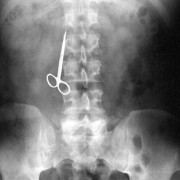

Можеби понекогаш се чувствувате виновно заради обилниот ручек што сте го изеле, но кога ќе видите што ставиле овие луѓе во својот стомак, ќе сфатите дека вие немате причина да се грижите. Барем не сте изеле батерии. Иако можеби имаат помалку калории, попрво би јаделе вкусни слатки со многу масти отколку киселински раствор. Луѓето имаат изедено некои многу чудни нешта…